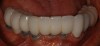

Figure 44 – Smile of a patient with a dental implant.

Figure 44

Many patients struggle with ill-fitting removable full and partial dentures. The resulting conditions of periodontal bone loss, malnutrition, and overall low self-esteem can occur. Fortunately, better options exist with today’s implant technology. As patients are counseled on dental implant procedures, they can be assured that with basic home care protocols, their dental implant investment can have a high rate of success. Furthermore, implants will not decay once osseointegrated, so crowns do not need to be replaced due to recurrent caries (Figure 44).